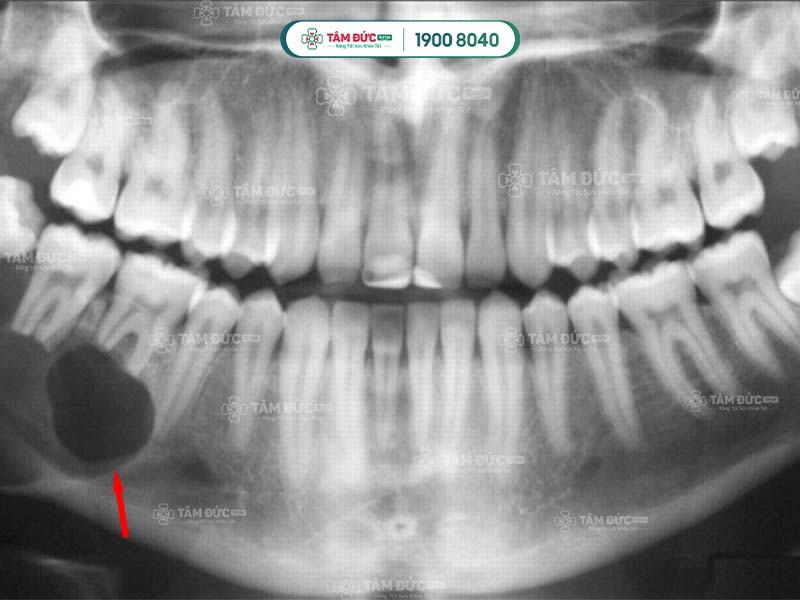

Tâm Đức Smile là nha khoa uy tín để Quý khách gửi gắm sức khỏe răng miệng của mình. Khi chữa tủy răng bị hoại tử, Quý khách sẽ được thăm khám kỹ lưỡng về ống tủy và tình trạng răng bằng máy móc chuyên dụng.